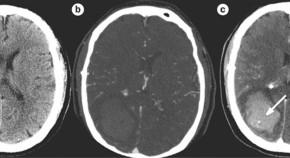

• Clinical trials aimed at preventing hematoma expansion in patients with intraparenchymal hemorrhage have failed to show benefit from experimental intervention. Novel methods for identifying those patients at the highest risk of hemorrhage growth might enable better patient selection and, hence, increase the chance of demonstrating an improvement in clinical outcome.

• Kyra Becker

• David Tirschwell